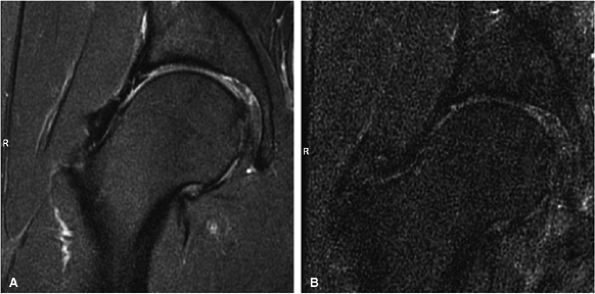

![]() |

|

FIGURE 1.26 ● Hip examination, coronal fast spin-echo proton density-weighted image with FatSat (TR 3100, TE 41). (A) Images acquired with a four-channel cardiac array coil. (B) Images acquired with a body coil. The signal-to-noise improvement with the array coil is at least 100%.